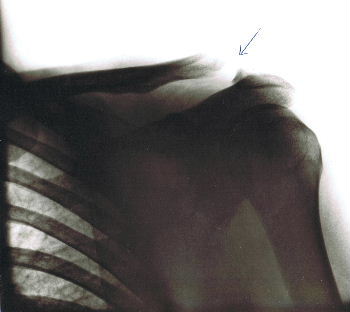

1980 - mein bis Dato einziger schwerer Sturz (Schultereckgelenk war im Eimer) und Schuld hatte ein Mopedfahrer ohne Führerschein